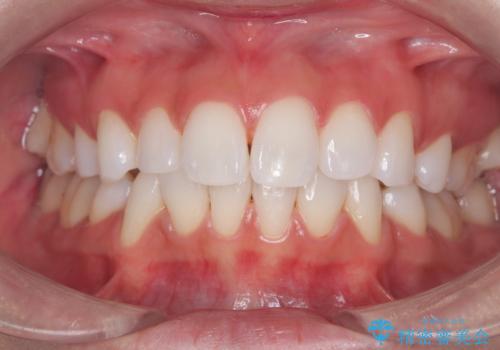

[ セラミック治療 ] 前歯の見た目を改善したい

担当医 大元洋佑